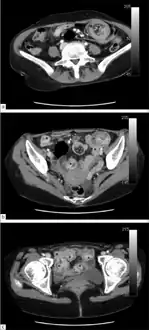

Axial CT scans of the abdomen showing multiple intussusceptions in the jejunum